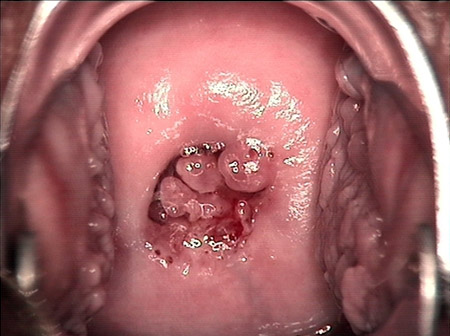

• CIN 2-3CIN 2-3

• CIN 2-3 碘著色后CIN 2-3 碘著色后

• CIN 2-3 leep術后CIN 2-3 leep術后

• CIN 2-3 修復后CIN 2-3 修復后

• CIN 2-3 修復后(圖2)CIN 2-3 修復后(圖2)